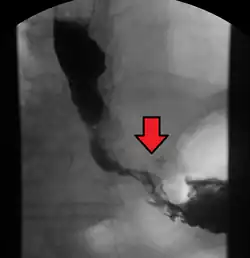

![]() Endoscopia de un paciente con adenocarcinoma de esófago localizado en la unión gastroesofágica. | ||